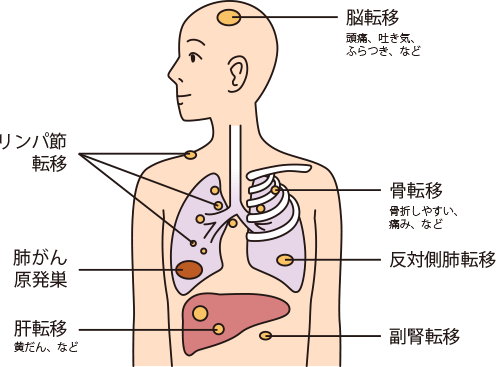

肺がんに特有の症状というものはありません。呼吸器に関係する症状(咳、痰、血痰、胸の痛み、息切れ、声のかすれなど)のほか、呼吸器以外の症状(肩の痛みや凝り、しゃっくりなど)が現れることもあります。また、転移した場所の症状が呼吸器に関係する症状よりも先に現れる場合もあります。脳転移による頭痛、めまい、吐き気、嘔吐、ふらつきや、骨への転移からくる痛みなどです。

骨に転移すると疼痛、病的な骨折が起こります。脳に転移すると、脳がむくむため頭痛や吐き気が起こります。転移部位が中枢だと手足のまひ、小脳だとふらつき、部位によっては言語障害や意識障害が起こることがあります。

肺腺がんは4つのタイプに分けられる肺がんの中で最も発生頻度の高いがんで、肺がん全体のおよそ半数が腺がんであるといわれています。

女性やタバコを吸わない人にも多く、肺の奥のほうのこまかく枝分かれした先にできるため、初期には症状がないことが肺腺がんの特徴です。がんが進行すると、胸痛、咳、痰などの一般的な呼吸器疾患でもみられる症状があらわれますが、肺腺がんに特有の症状はありません。また、肺とは関係がないと思われる頭痛やふらつきといった症状がみられることがあります。これは脳への転移による症状ですが、この他にも転移した臓器にさまざまな症状がみられることがあります。

肺腺がんが転移しやすい臓器は脳、骨、肝臓、肺、副腎、リンパ節です。肺転移の場合、肺の中の原発巣とは異なる場所に新たながんが生じます。

肺には多くの血管やリンパ管が集まっているため、肺からほかの部位への転移、ほかの部位にできたがんから肺への転移、どちらも起きやすいといえます。

肺には多くの血管とリンパ管が集まっているので、肺がんは血行性、リンパ行性に転移しやすく、特に脳、骨、肝臓、副腎、リンパ節などが好発部位です。

肺がんの骨転移、副腎転移、皮膚転移、脳転移

肺がんは比較的転移しやすく、骨、脳、肝臓、副腎、リンパ節などが好発部位です。

転移すると、部位に応じていろいろな症状が現れます。

脳に転移するとむくみが生じ、頭蓋骨内の圧力が高まって、頭痛や吐き気が起こることがあります。肝臓に転移すると、全身のだるさや、体が黄色くなる黄疸が現れることがあり、左右の肺を隔てる縦郭に転移すると、上大静脈が圧迫されて上半身がむくむことがあります。さらに骨の転移では、転移した部位に強い痛みを感じたり、骨折したりします。